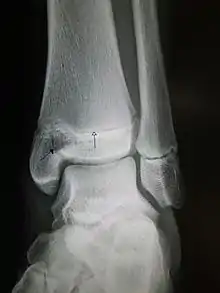

كسور سالتر هاريس

كسور سالتر هاريس عبارة عن كسور تتضمن صفيحة المشاشة أو لوحة نمو العظام.[1][2][3] يعتبر سبب شائع للإصابة عند الأطفال، حيث يحدث في حوالي 15% من كسور العظام الطويلة في مرحلة الطفولة.

يوجد 9 أنواع من كسور سالتر هاريس، من النوع الأول للخامس توصف ب روبر B سالتر وW روبرت هاريس، في عام 1963 والأنواع النادرة من 6-9 تم إضافتها لاحقا.

النوع الأول: كسر عرضي خلال لوحة النمو ويشار أيضا إلى (صفيحة النمو) بنسبة 6%.

النوع الثاني: الكسر خلال لوحة النمو والكردوس مع الحفاظ على المشاشة بنسبة 75%، يحتاج من 2-3 أسابيع للالتئام.

النوع الثالث: كسور خلال لوحة النمو والمشاشة مع الحفاظ على الكردوس بنسبة 8%.

النوع الرابع: كسر خلال الأنواع الثلاثة للعظم؛ لوحة النمو والمشاشة والكردوس بنسبة 10%.

النوع الخامس: كسر ضغطي للوح النمو (مما يؤدي إلى انخفاض في الفضاء المحفوظ بين المشاشة والكردوس على أشعة اكس) بنسبة 1%.